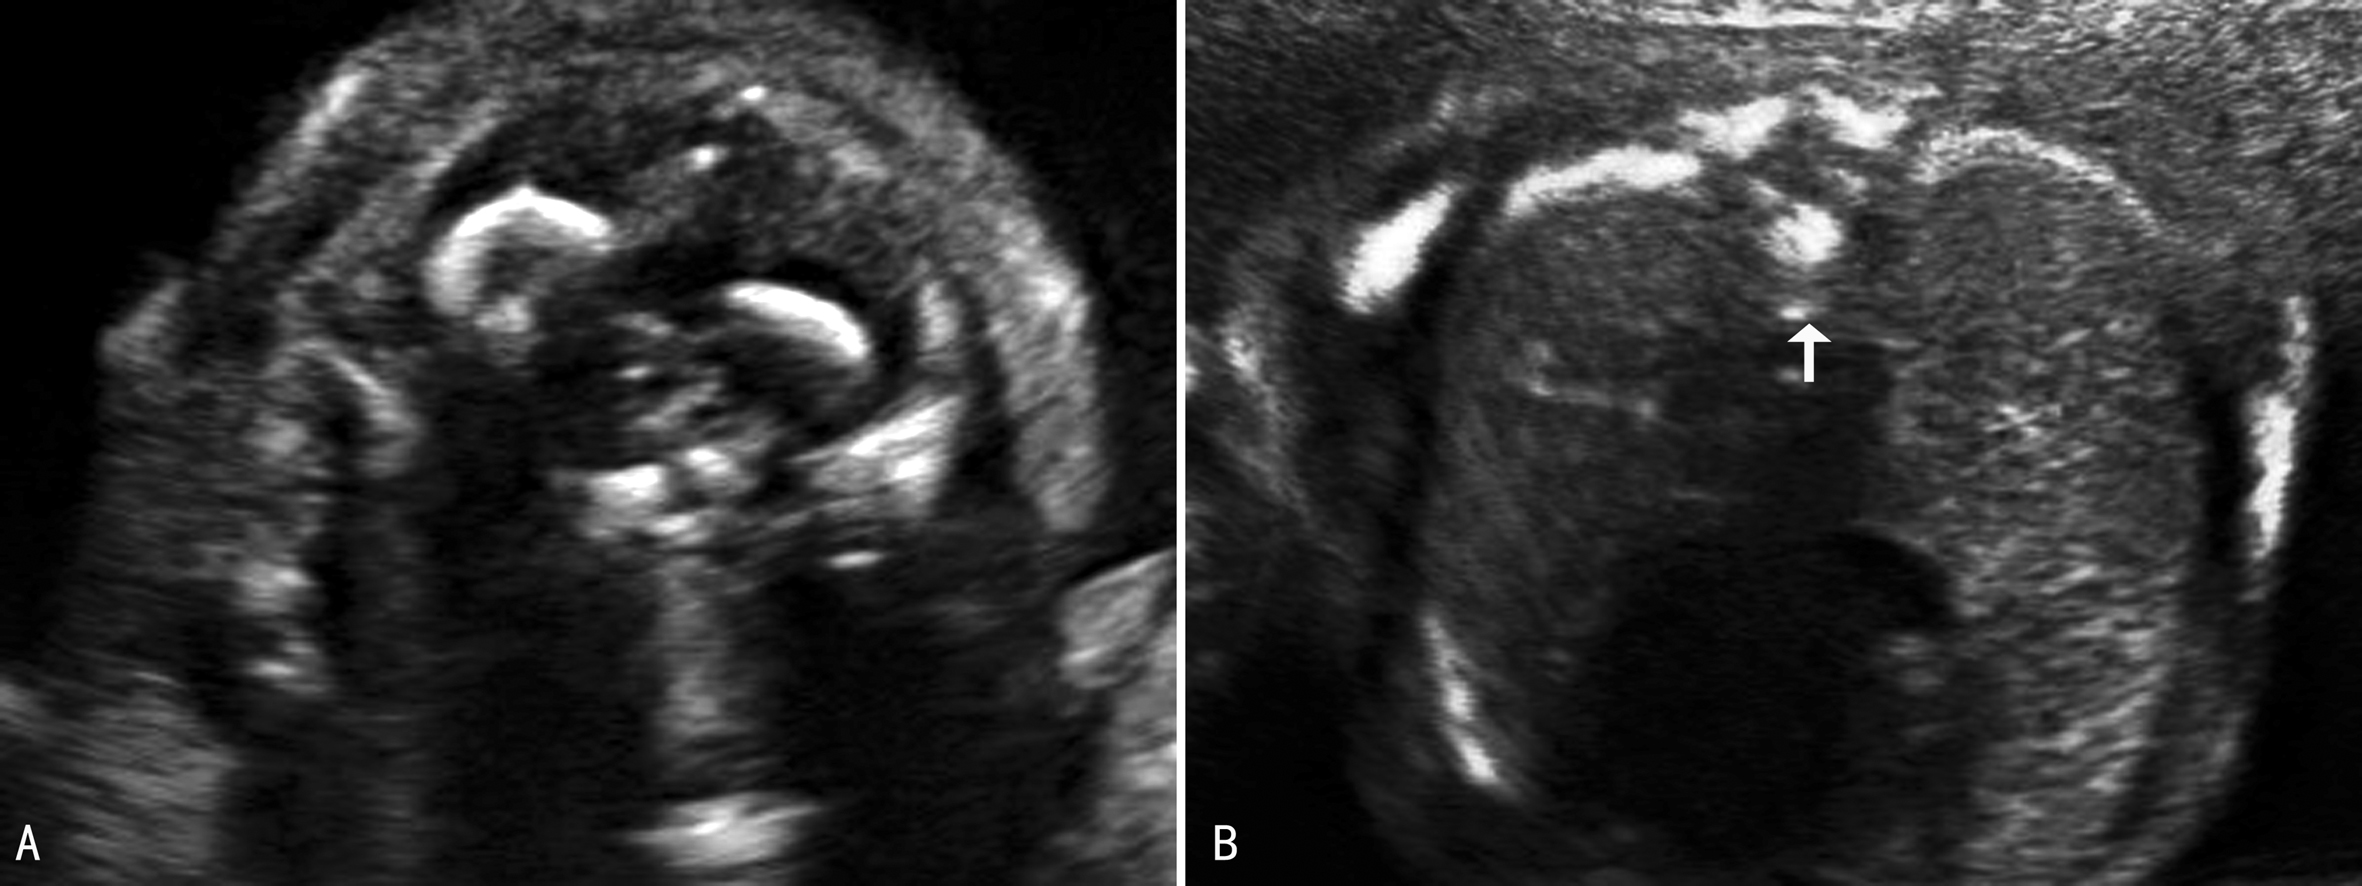

超声显像检查时需要观察矢状切面、横切面和冠状切面(图3,4)。矢状切面显示椎体及一侧椎弓的骨化中心呈现两条串珠状的平行线,在骶尾部收拢合并,因为一个切面只能显示一侧的椎弓,需动态扫描使两侧椎弓都能显示;[f2] 横切面的扫查需要耐心仔细从颈椎到骶尾部依次进行,不同的椎体超声表现不同,第一颈椎呈四边形或圆钝的三角形(图3A),其他呈现等腰三角形,尖端为椎体,指向胎儿腹侧(图3B,图4C、D)。冠状切面,声束靠近皮肤显示两排平行的骨化中心,是双侧椎弓,声束再向胎儿腹侧扫查,可显示一排椎体(图5),透明三维显示可以直观地显示胎儿脊柱的空间结构和形态(图6)。扫查时要注意覆盖在脊柱上的皮肤的完整性,以免遗漏微小的脊柱裂或者隐形脊柱裂,隐形脊柱裂有时仅表现为皮肤鼓起的小泡状无回声。

图4 腰椎横断面(C)及骶椎横断面(D)

图5 脊柱冠状切面声像图(箭头示髂骨翼,1为椎弓,2为椎体)